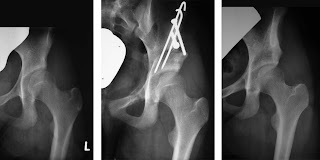

In most cases, the necrosis is a consequence of treatment and does not result from the dislocation itself. The necrosis can occur in the epiphyseal plate either laterally, centrally or medially (⊡ Fig. 3.165) [83], but most often laterally (⊡ Fig. 3.166).

This results in shortening of the femoral neck, or »head in neck position«, and overgrowth of the greater trochanter. The same shortening of the femoral neck and overgrowth of the greater trochanter is also seen with central necrosis, whereas medial necrosis results in a coxa vara. But the necrosis can also affect the acetabulum.

But this assumption now needs to be revised. In recent years we have observed several cases in which a normal hip during childhood has deteriorated into a distinctly dysplastic hip during puberty (⊡ Fig. 3.167).

Evidently, premature closure of the triadiate cartilage can occur during puberty so that the acetabulum no longer adequately matches the growth in size of the femoral head.